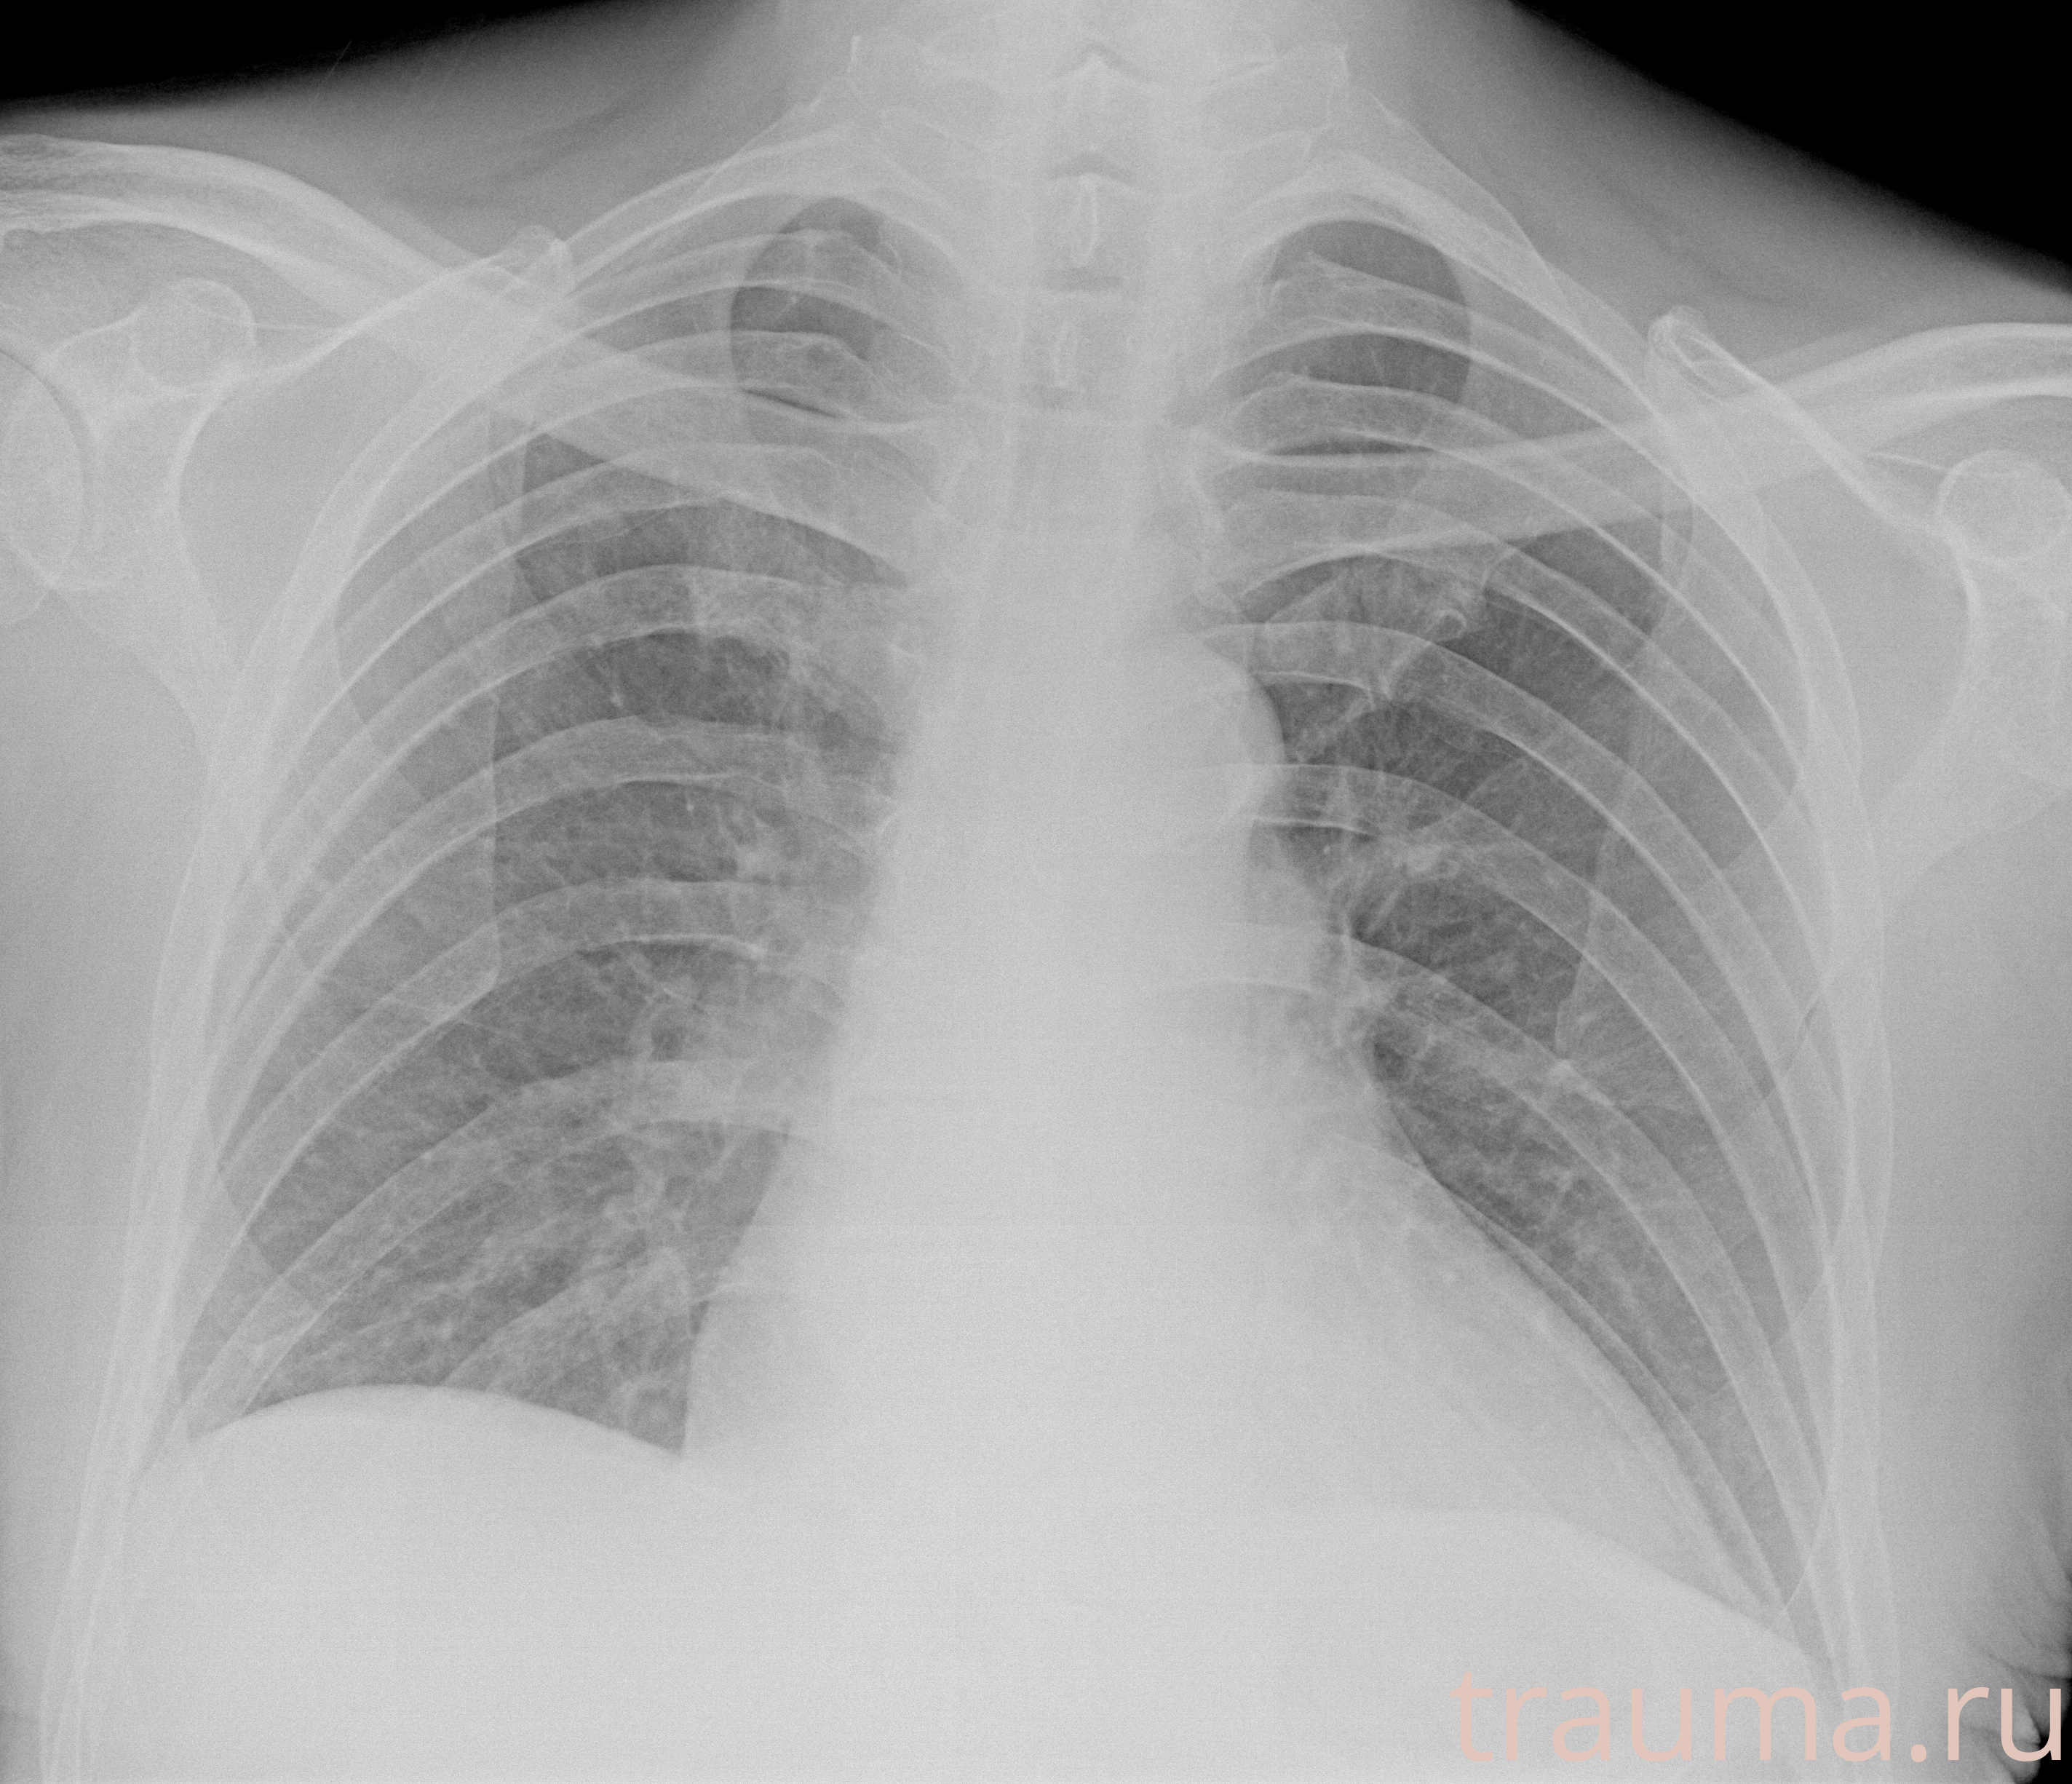

Рентгенограммы

Рентген на дому: по вашему адресу приезжает врач-рентгенолог, травматолог-ортопед с мобильным рентгеновским аппаратом, проводит диагностику травмы или заболевания, делает необходимые рентгенограммы, дает рекомендации по дальнейшему лечению. Получить качественные снимки в домашних условиях возможно благодаря уникальной методике, разработанной МосРентген Центром для института  Склифосовского

Яркость: 1   Контраст: 1   Инвертировать: 0 Увеличение: 1

Перетаскивайте мышь вверх/вниз для контраста, влево/право для яркости. Прокрутка колесом изменяет масштаб. Нажмите Сбросить для возврата к исходному изображению. При увеличении держите мышь в той области, которую хотите рассмотреть.